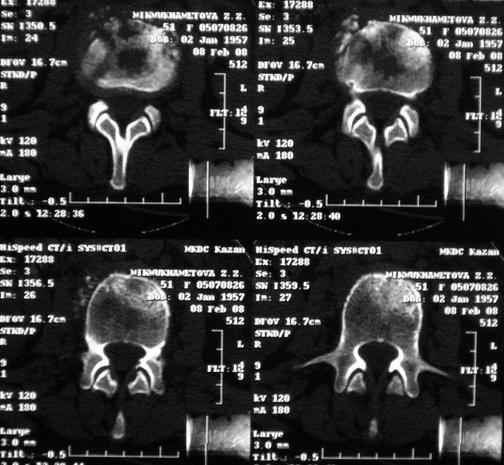

Отправляю MRI в динамике, снятые с пленки на фотоаппарат.

|

По данным представленных КТ и МРТ у больной имеется достаточно выраженная степень деструкции тел позвонков (около 30% общей костной массы тела позвонка), что определяет высокий риск возникновения патогических переломов и появления локальной кифотической деформации на этом уровне.